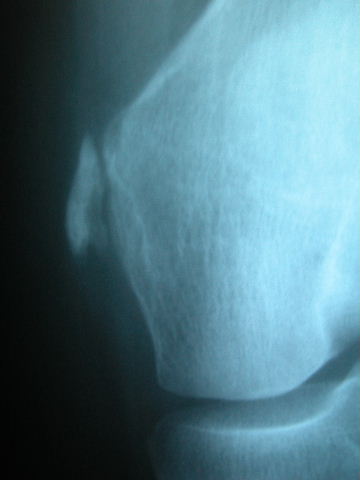

APR Gonartrosis